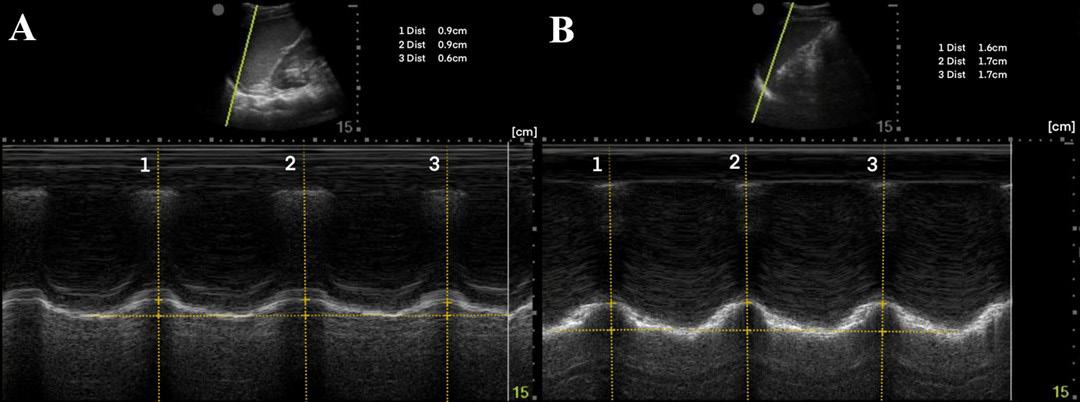

To measure diaphragmatic excursion the patient is first placed in a supine position. A curvilinear probe is placed in the midaxillary line and oriented cephalad to optimally visualize the inferior aspect of the lungs, diaphragm, and upper abdomen (ie, spleen or liver). Diaphragmatic excursion was quantified on M-mode imaging, with the M-mode cursor directed through the diaphragm. The amplitude of diaphragmatic excursion was measured from the baseline to the point of maximal excursion on the vertical axis (Image 1).

A 44-year-old man presented after a motorcycle collision and was found to have right-sided fractures of ribs 2-5 and 12 on computed tomography (CT). The patient continued to report severe pain after 100 micrograms (mcg) of intravenous (IV) fentanyl. M-mode of the right diaphragm was performed prior to SAPB and showed 5 millimeters (mm) of diaphragmatic excursion and a respiratory rate of 24 breaths per minute (BPM) (Image 2A). A right ultrasound-guided SAPB was performed with 20 milliliters (mL) of 1% ropivacaine. On re-evaluation approximately 60 minutes later, M-mode of the right diaphragm showed a respiratory rate of 16 BPM and 14 mm of diaphragmatic excursion (increase of 64%) (Image 2B). Increase in diaphragmatic excursion was calculated as the change in diaphragmatic excursion (14 mm minus 5 mm) divided by the post-block diaphragmatic excursion (14 mm).

report severe pain. M-mode of the left diaphragm was performed prior to SAPB and showed 8 mm of diaphragmatic excursion and a respiratory rate of 20 BPM (Image 3A). A left ultrasoundguided SAPB was performed with 20 mL of 1% ropivacaine. On re-evaluation approximately 60 minutes later, M-mode of the left diaphragm showed 17 mm of diaphragmatic excursion (increase of 53%) and a respiratory rate of 16 BPM (Image 3B).

A 50-year-old man presented with left-sided chest wall pain after a fall four days prior when intoxicated and was found to have fractures of ribs 6-9 on CT. The patient initially rated his pain 10/10 and was given 100 mcg of IV fentanyl. Pain continued to be 10/10 and a SAPB was performed for pain control. A left ultrasound-guided SAPB was performed with 20 mL of 0.5% bupivacaine combined with 10 mg of dexamethasone. The patient’s pain 60 minutes after the block was 2/10. A diaphragmatic POCUS was performed both before and 60 minutes after the SAPB block. The initial respiratory rate was 20 BPM with 19 mm of diaphragmatic excursion (Image 4A). After 60 minutes from the SAPB, the patient’s respiratory rate was 14 BPM with a diaphragmatic excursion of 32 mm (increase of 41%) (Image 4B).

Image 2. (A) Pre-block demonstrating right-sided diaphragmatic excursion of 5 millimeters (mm) (average of two excursions). (B) Post-block demonstrating right-sided diaphragmatic excursion of 14 mm (increase of 64%). Image 3. (A) Pre-block demonstrating left-sided diaphragmatic excursion of 8 mm (average of three excursions). (B) Post-block demonstrating left-sided diaphragmatic excursion of 17 mm (increase of 53%). Image 4. (A) Pre-block demonstrating left-sided diaphragmatic excursion of 19 mm. (B) Post-block demonstrating left-sided diaphragmatic excursion of 32 mm (increase of 41%).